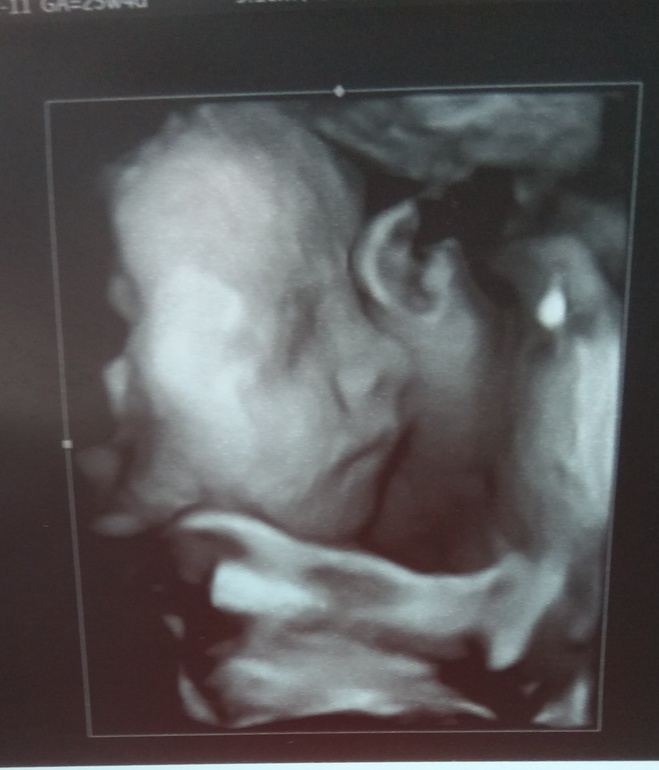

26 неделя 23 год

26 неделя 23 год 113 фотографий